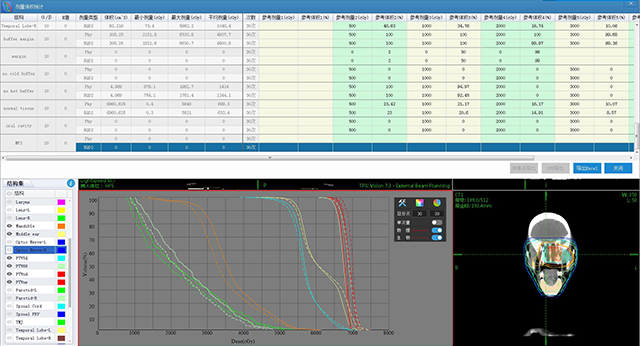

ж”ҫз–—еӯҰ科е»әи®ҫ

иЈ…еӨҮз»ҙдҝқе’ҢиҙЁжҺ§ж•ҲеҠі

иӮҝзҳӨж”ҫз–—дҝЎжҒҜеҢ–дә§е“Ғ

дә§е“ҒдёҺж•ҲеҠі

дә§е“ҒдёҺж•ҲеҠі